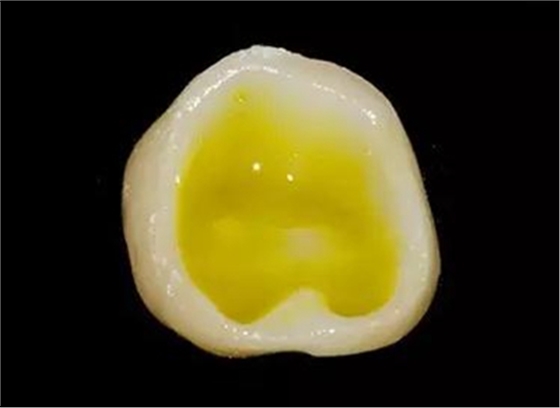

牙體制備完成后的牙合面觀

牙合面觀察牙體預(yù)備之后的情況。

軸壁按要求預(yù)留0.8 mm 寬度。